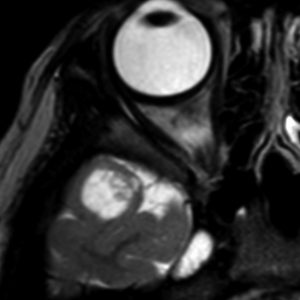

第4室床過誤腫の典型例です

新生児期より動作停止と右眼瞼のちく搦,4ヶ月で右眼の閉眼と口角の引きつれ(顔面けいれん)が目立つようになりました。2歳時には数十秒ごとに発作を繰り返していました。

MRIでは橋の背側(第4脳室床)にT1/T2で等信号の隆起(腫瘤)がみられました。